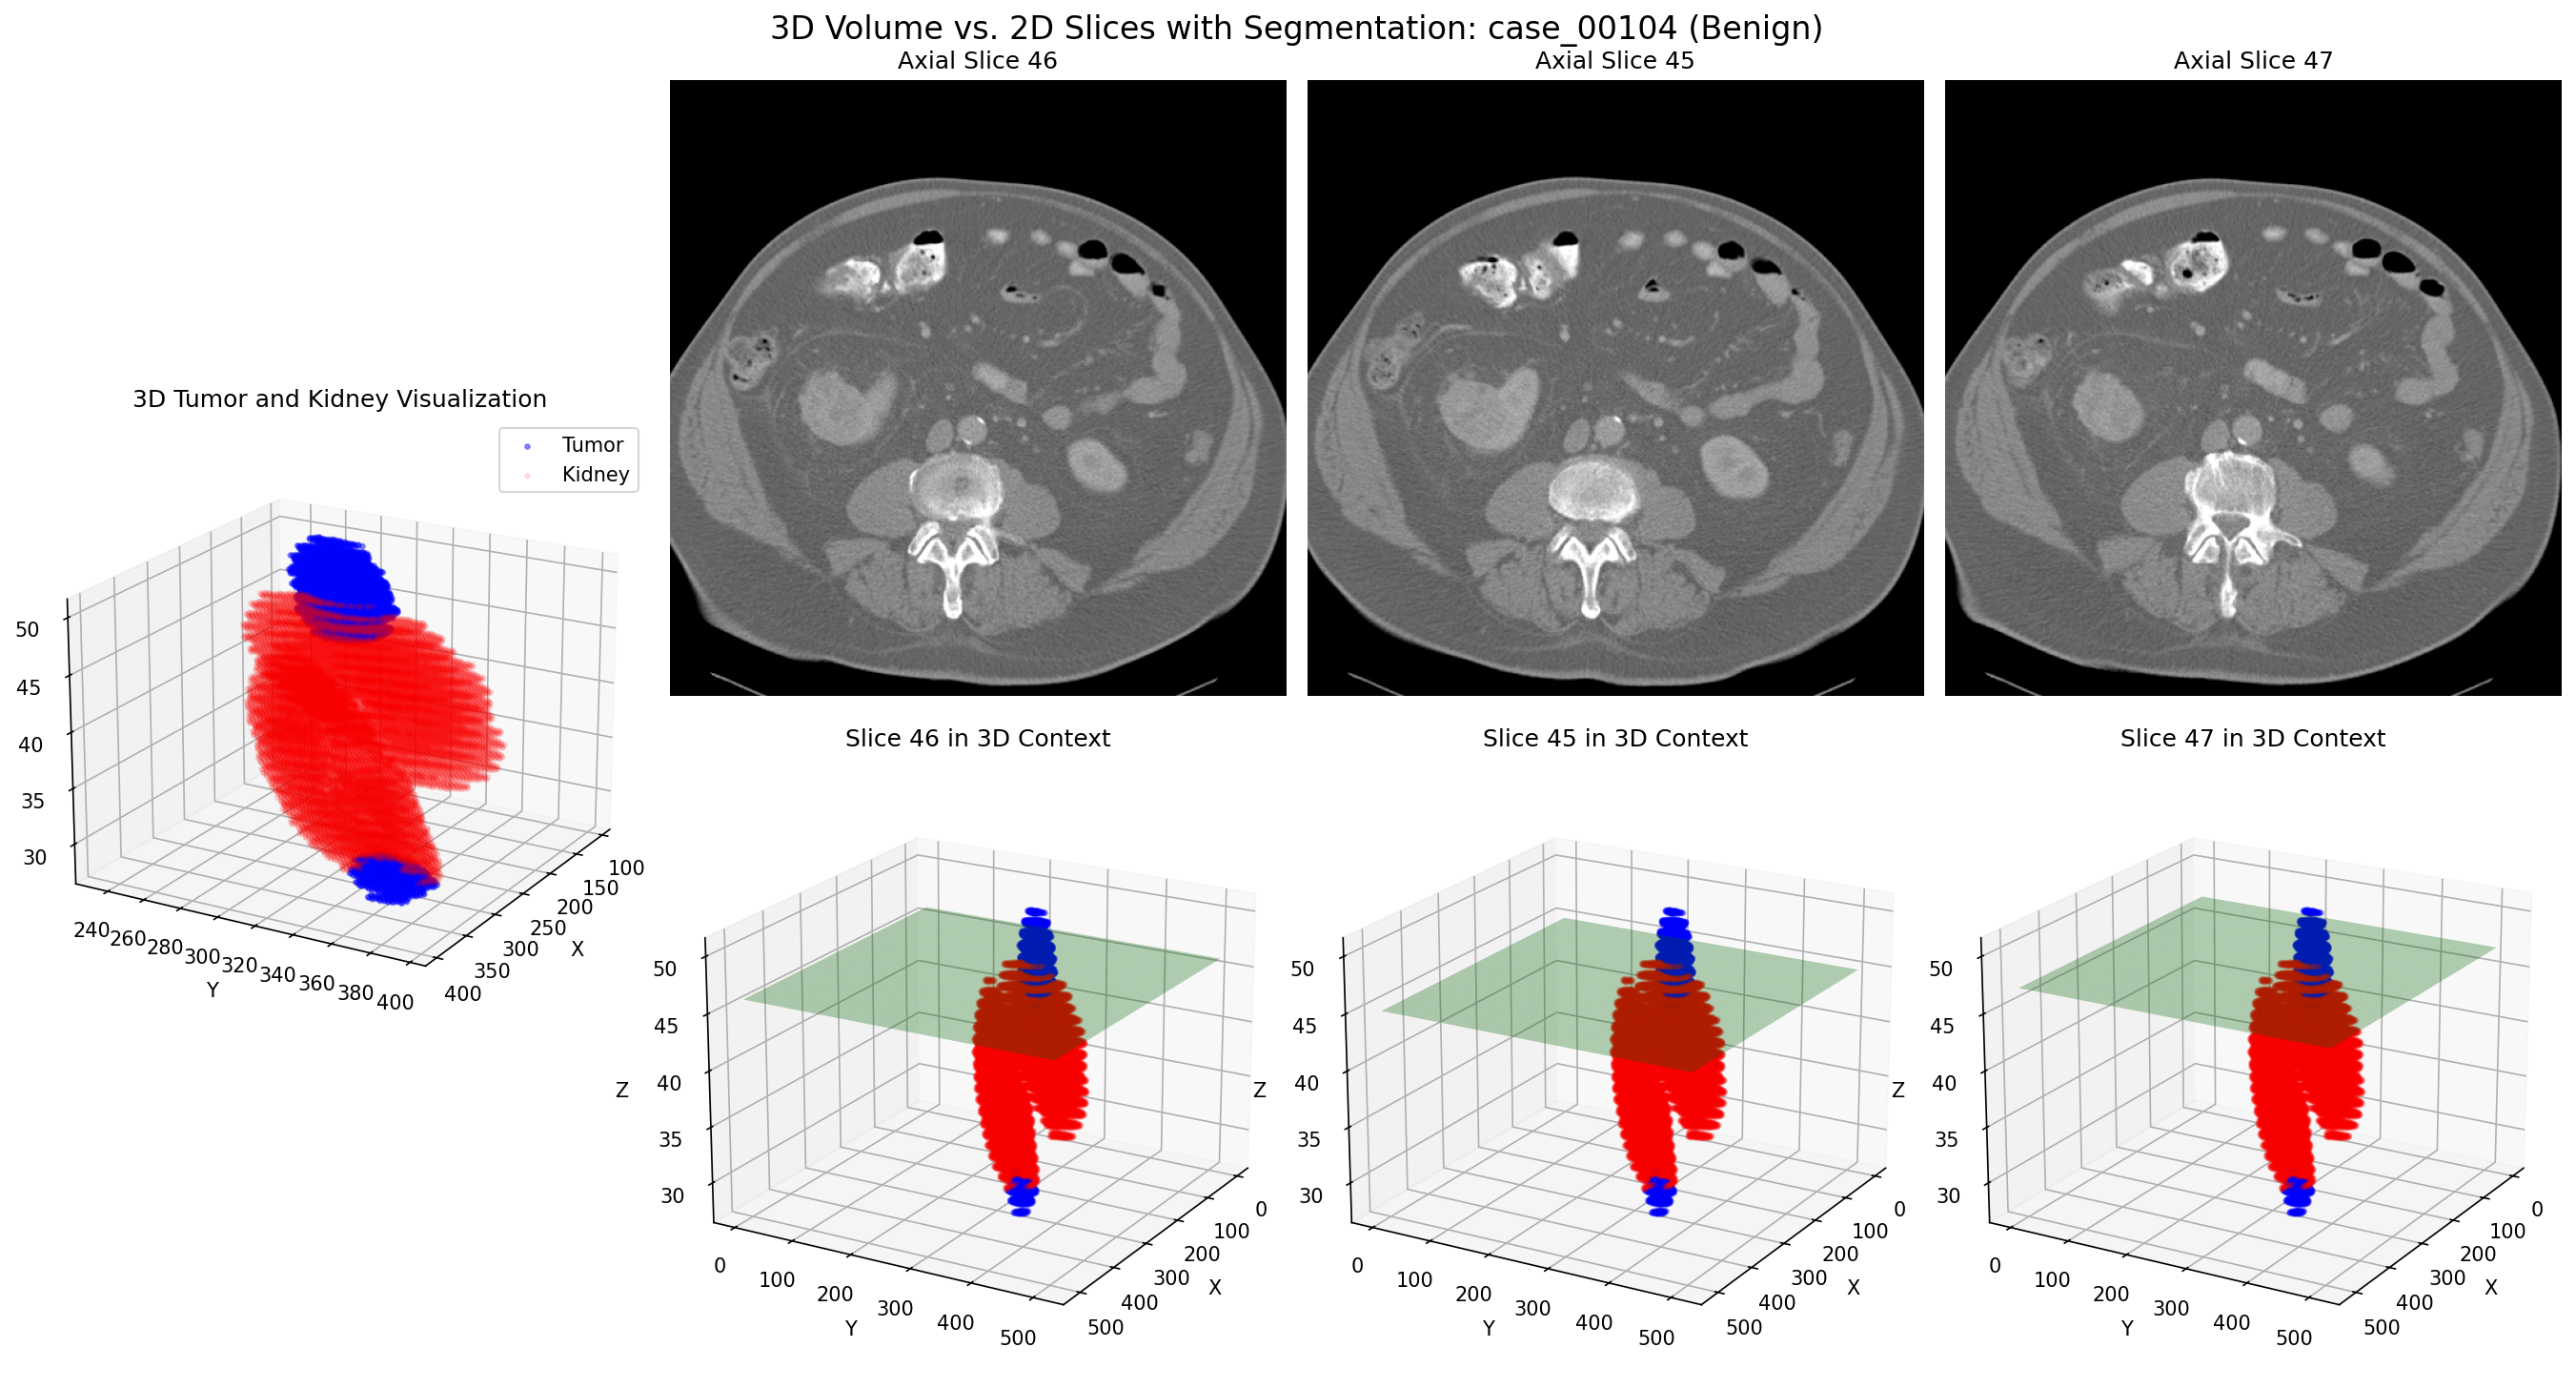

Case 00104: Advanced malignant tumor with 3D volume visualization (top) and optimal 2D slice selection (bottom)

Additional Case Study: Malignant Tumor

The diagram to the right illustrates how our approach extracts the most relevant 2D slices from a 3D volume, optimizing both the quantity and quality of training data.

Diagram showing how 3D volumetric data is transformed into multiple 2D slices along different planes for optimal model training

These side-by-side comparisons show the relationship between 3D tumor volumes (top row) and their corresponding 2D slices (bottom row) for both malignant and benign cases. Our algorithm intelligently selects the most informative 2D slices from each 3D volume, capturing the key diagnostic features while generating multiple training examples from a single case.

Key insight: By converting each 3D case into multiple 2D slices, we effectively increased our training data by a factor of 8-10, with each slice carrying distinct morphological information about the tumor.